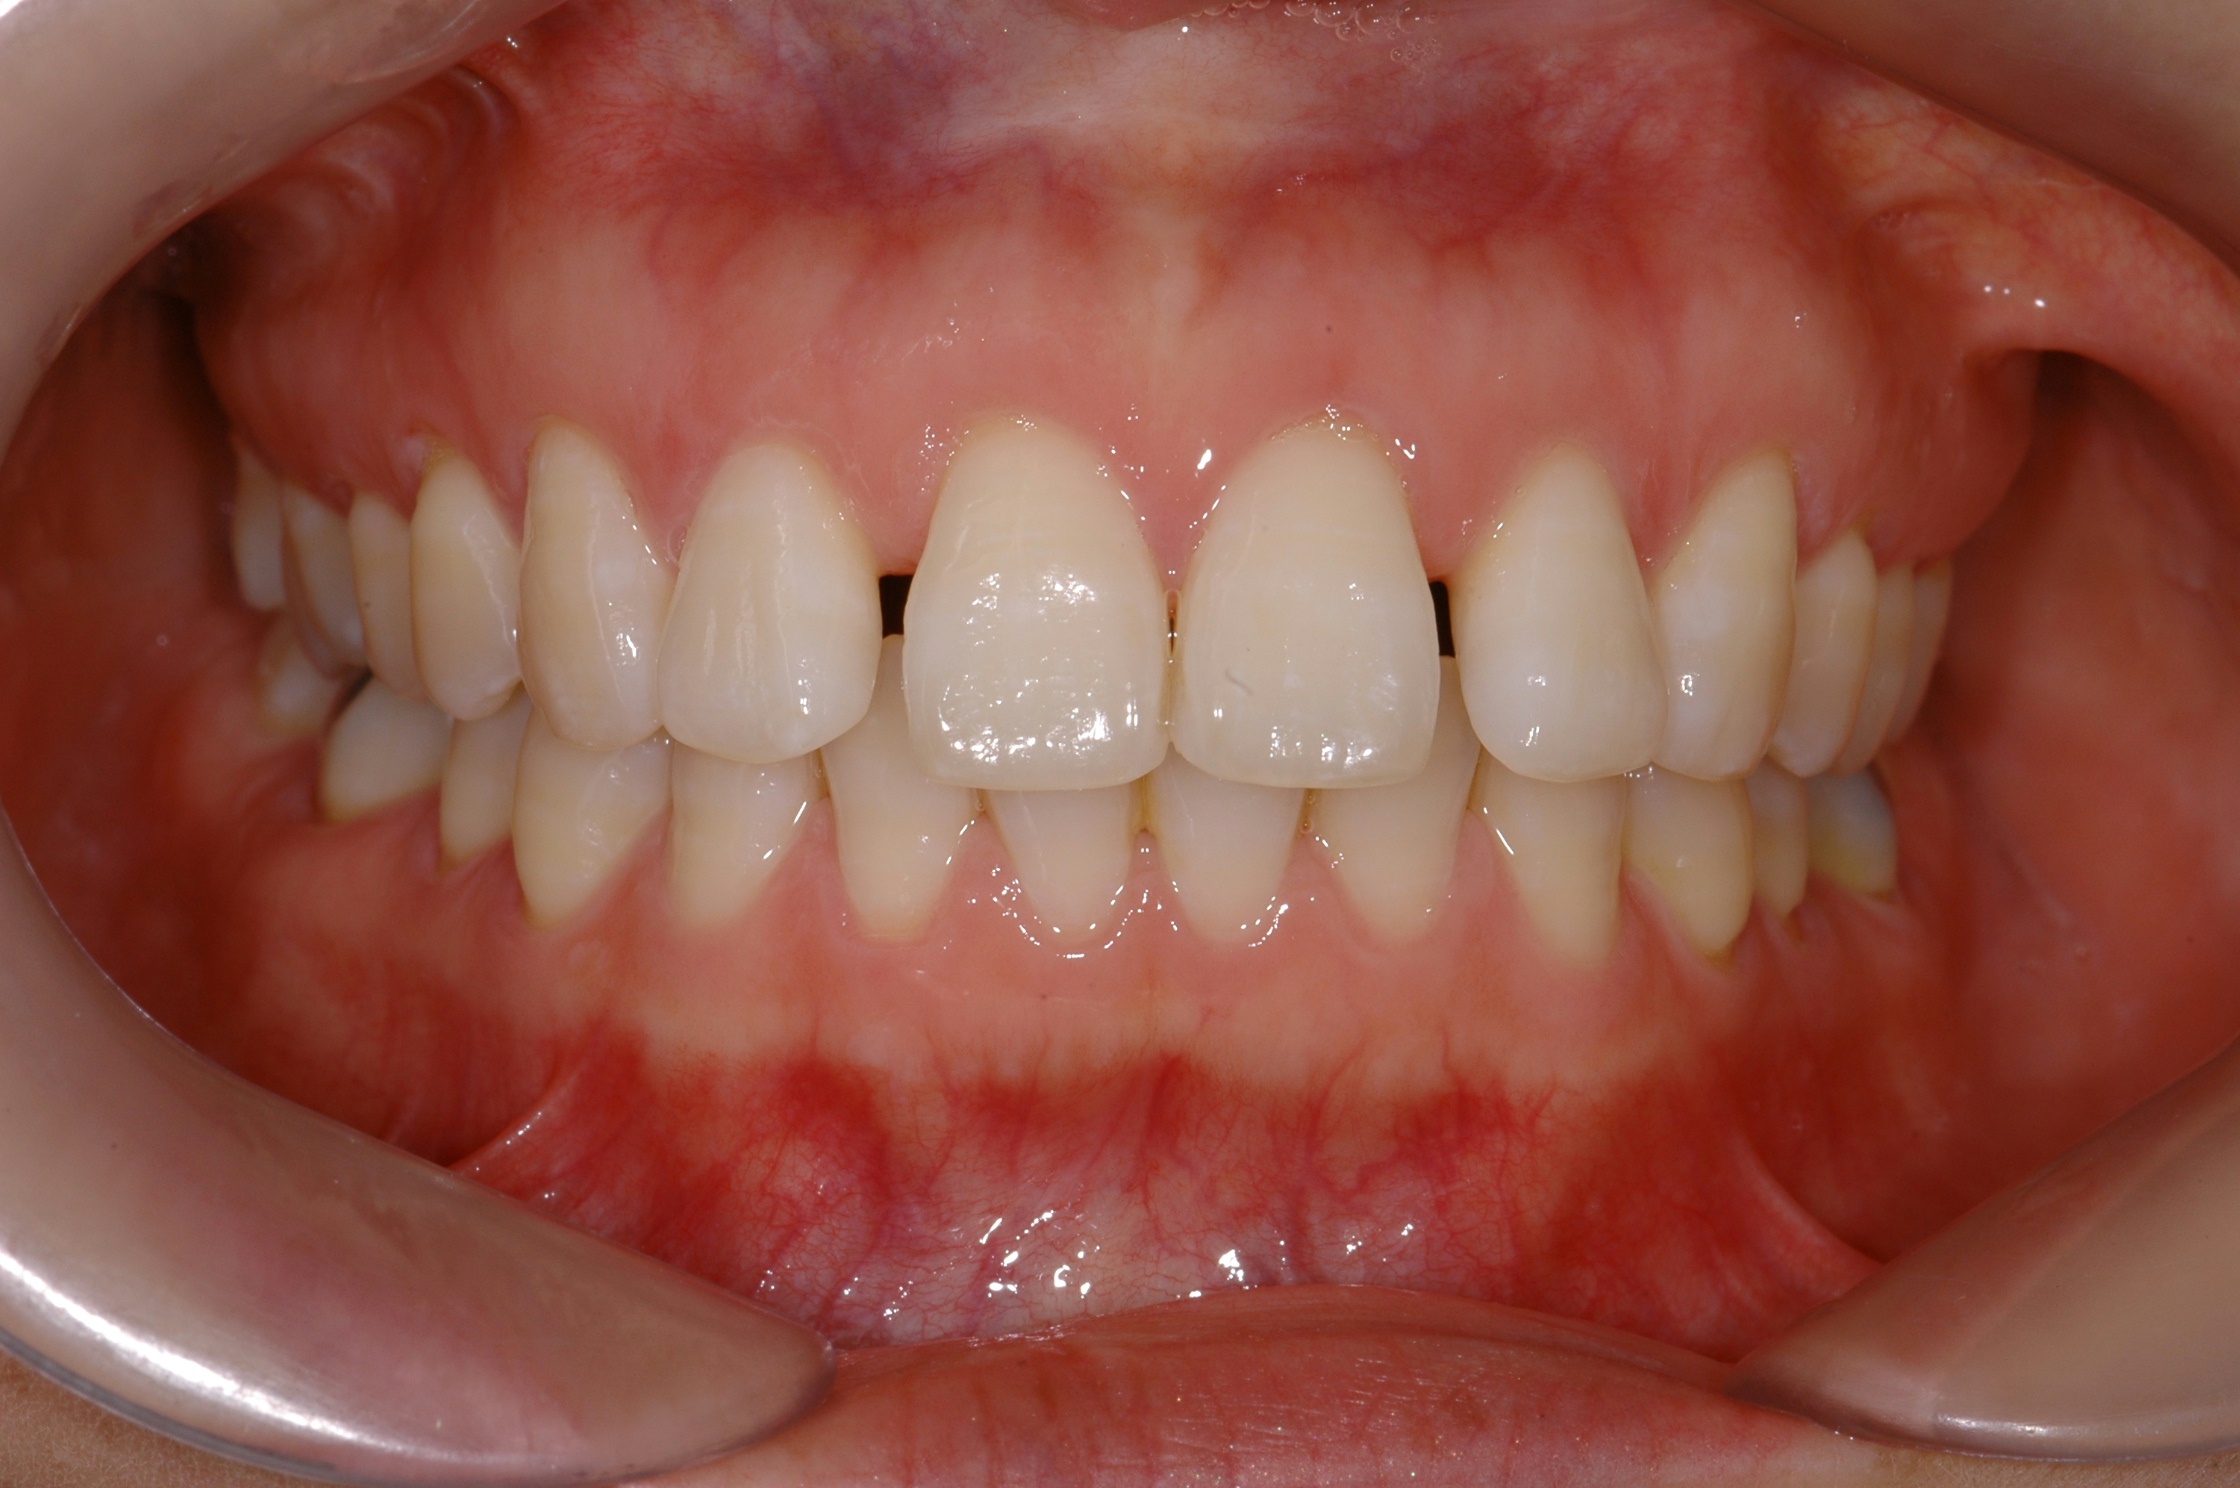

치료 후 사진입니다.